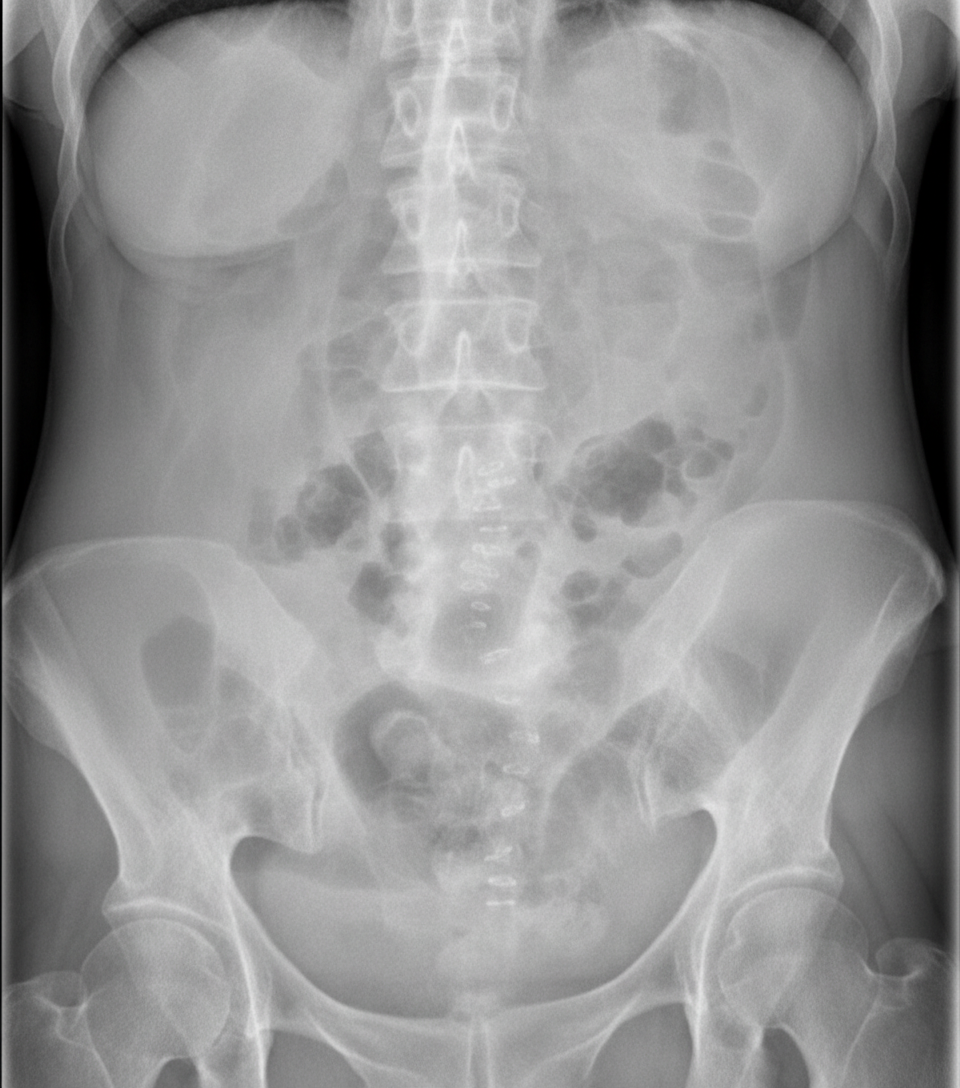

A 75-year-old man is brought to the emergency department after 2 days of severe diffuse abdominal pain, nausea, vomiting, and lack of bowel movements, which has led him to stop eating. He has a history of type-2 diabetes mellitus, hypertension, and chronic obstructive pulmonary disease. Upon admission, his vital signs are within normal limits and physical examination shows diffuse abdominal tenderness, distention, lack of bowel sounds, and an empty rectal ampulla. After initial fluid therapy and correction of moderate hypokalemia, the patient's condition shows mild improvement. His abdominal plain film is taken and shown. Which of the following is the most appropriate concomitant approach?